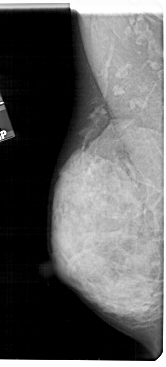

A_1807_1.LEFT_MLO

LEFT_MLO LINES 5491 PIXELS_PER_LINE 2476 BITS_PER_PIXEL 12 RESOLUTION 43.5 NON_OVERLAY

A_1807_1.LEFT_CC

LEFT_CC LINES 5056 PIXELS_PER_LINE 2356 BITS_PER_PIXEL 12 RESOLUTION 43.5 NON_OVERLAY